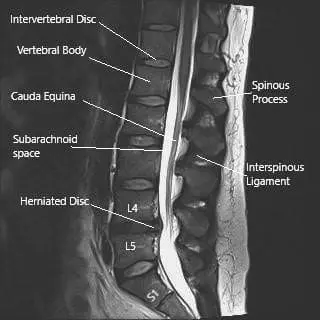

MRI image of the lumbosacral spine in sagittal section showing herniated intervertebral disc at L4-L5 level.

The sciatic nerve’s large size and long course make it particularly vulnerable to compression or injury. The most common cause of irritation is a herniated disc at the L4–L5 or L5–S1 levels, which can compress one or more of the contributing nerve roots. Other causes include spinal stenosisdegenerative disc diseasepiriformis syndrome, and direct trauma.

MRI is the most effective imaging tool for assessing sciatic nerve pathology. It can detect disc herniations, spinal canal narrowing, and nerve root compression at the lumbosacral level. CT scans and electromyography (EMG) may also be used to identify bone-related causes or assess nerve function.

An MRI of the lumbosacral spine often reveals the source of compression — most commonly a herniated disc at the L4–L5 level pressing on one of the contributing nerve roots.